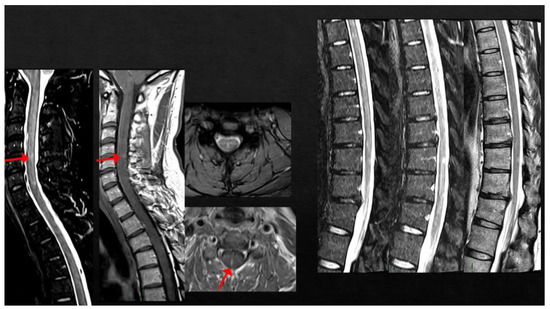

4. MS Onset after Vaccine Exposure